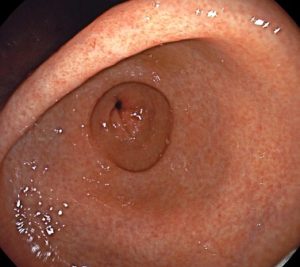

La gastritis es la inflamación del revestimiento del estómago. Puede ser aguda, que es de corta duración, o crónica, cuando persiste durante un período prolongado. La causa más común de gastritis es una infección bacteriana por Helicobacter pylori, aunque también puede ser causada por el uso excesivo de medicamentos antiinflamatorios no esteroideos (AINEs), consumo excesivo de alcohol, estrés, fumar, trastornos autoinmunes u otras enfermedades.